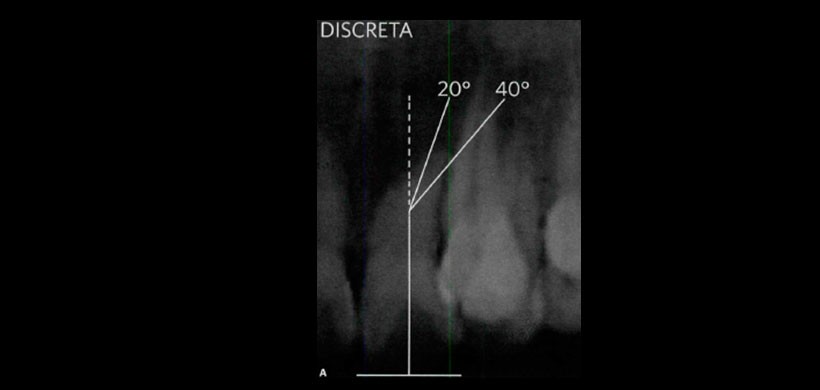

Fig 3. Dilaceración radicular tipo SEVERA, se considera una angulación mayor a 60°.